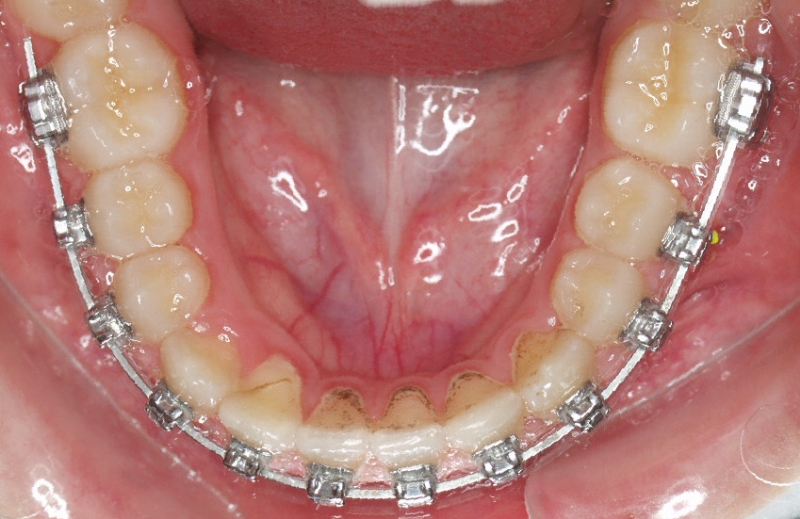

Clase II paciente 15 años

La paciente O.O. acude a nuestra consulta por:

– Canino 13 e incisivo lateral 42 en posición ectópica.

– Canino 23 incluido.

Con lo que decide realizarse un tratamiento de ortodoncia de duración de 24 meses con brackets damon Q.